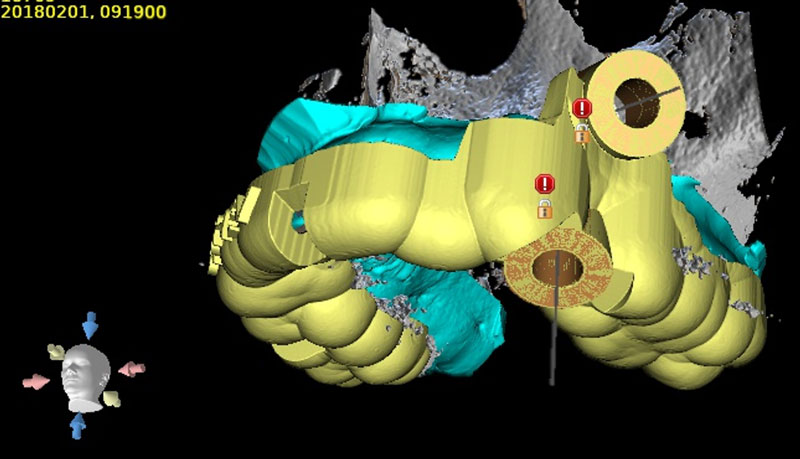

В программе-планировщике мы выбираем размеры имплантатов, расставляем их на виртуальной модели челюсти пациента в безопасном положении, учитывая расположение крупных нервов, гайморовых пазух и других важных анатомических образований. По этим данным программа создают точный хирургический шаблон, в котором заложена вся информация о положении имплантатов: глубина и углы наклона, именно те, которые врач спланировал в программе. На планирование хирургического шаблона требуется всего лишь 1 рабочий день.